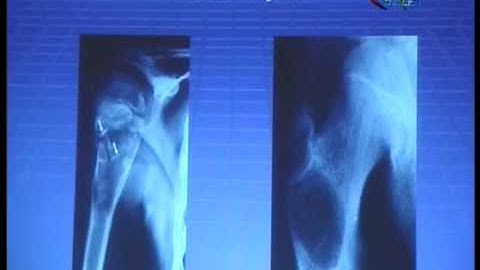

Bone Tumor A Z Part 2 Series 2 with Mohamed Shanah